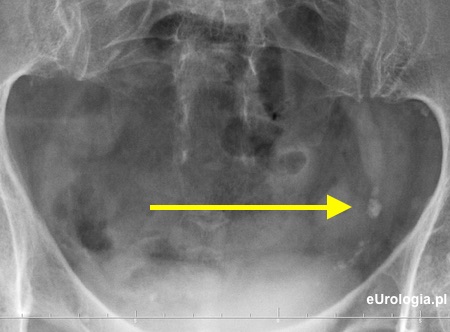

Cień wapienny o wumiarach 9x7 milimetrów w miednicy małej po stronie lewej

Złóg w dolnym odcinku moczowodu.